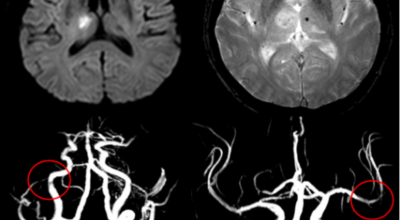

뇌 속에 혈액을 제공하는 혈관이 있는데, 이 혈관이 막히면 정상적으로 지급되어야 할 만큼의 혈액이 뇌까지 도달하지 못하여 뇌조직이 제 역할을 수행하지 못하는 것을 말해요. 이 시간이 지속될 경우 몸의 여러 곳에 지장이 생기며 이것을 뇌경색이라고 해요.

뇌경색의 주된 원인은 혈전입니다. 혈전이란 혈관 속에 피가 굳어진 덩어리를 얘기하는데 이것이 혈관을 막는 것이 뇌경색에 큰 영향을 준다고 해요. 평균적으로 많이 나타나는 연령대는 5~60대입니다. 뇌경색은 양쪽 뇌에 모두 생기는 것이 아니라 주로 한쪽 뇌에만 발생하지만, 주로 한쪽 팔다리가 마비되거나 얼굴 근육이 굳어버리기도 해요.

뇌경색이 생기는 원인은 아주 다양해요. 뇌경색은 뇌의 혈관이 막혀 뇌의 일부가 죽는 질병을 말하는데 주로 뇌경색의 원인은 혈전이며, 혈전으로 인해 뇌혈관이 막히는 위험 인자는 혈전을 발생하게 해요. 또한 동맥경화나 심장병, 혈관박리, 뇌혈관 기형 등으로 말미암아 생기게 될 수 있다고 하며 대부분이 60세 이상의 고령층에서 빈번히 나타나는 질환으로 알려져 있답니다.

뇌경색 증상이 처음 나타난 후 4-5시간이 경과하지 않았다면 주사 제제를 통한 혈전용해술을 시도해 볼 수 있어요. 24시간이 경과하지 않았고 대뇌혈관이 막힌 것을 확인하였다면 막힌 혈관에 대하여 기계적 재개통술을 시도할 수 있어요.